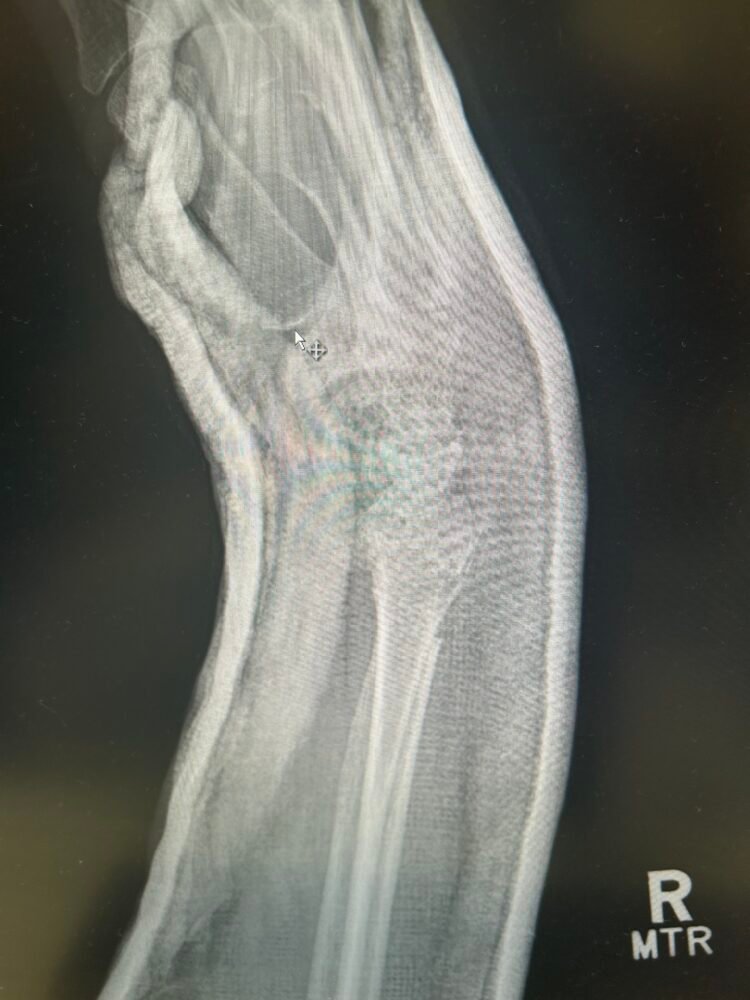

The title of this post mentions a glitch and that would be that I had a fall and broke my wrist quite badly and needed surgery to insert plates . This has meant that I have not been able to do any of the packing up and removal of the kitchen. It is extremely frustrating to say the least.